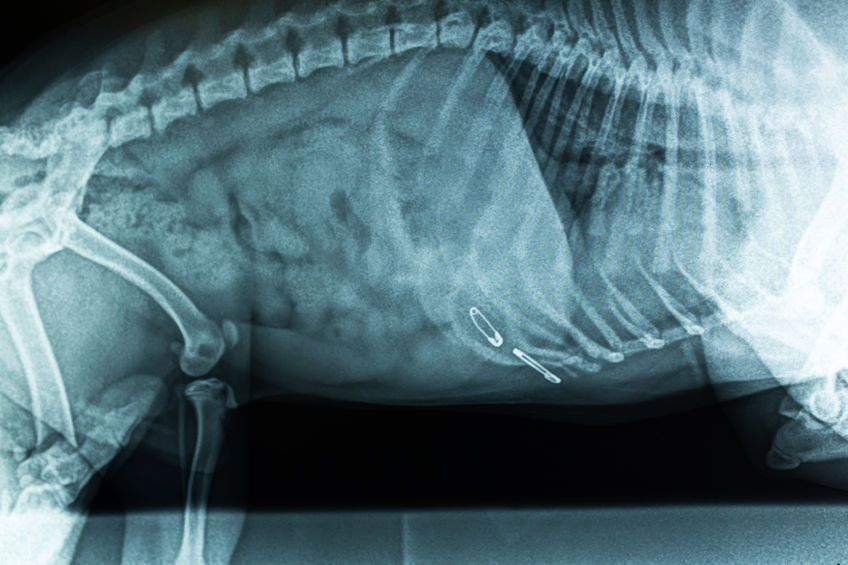

Weitreichend sind auch das Auslegen oder das Präparieren von Gegenständen wie Wurzeln oder Bodenflächen gespickt mit Schrauben, Nägeln, Scherben, Metallsplittern und Nadeln oder anderen scharfkantig tiefgreifend verletzende arglistigen Beköderungsmitteln.

Nagelfallen Präpariertes Fleisch, oder mit Nägeln und Nadeln gespickte Lockmittel, ebenso als Trittfalle nagelgespickte Baumwurzeln, Bretter oder Erdflächen

Scherben/ Glassplitter/ Rasierklingen Eingearbeitet bspw. in präparierten Futtermischungen (Fleischbällchen, Fleisch- oder Obststücke usw.), um als Lockfutter durch Tiere aufgenommen werden zu können um im Körper schwerste oder tödliche Verletzungen herbeizuführen, oder auch im Erdboden gespickt, um Verletzungen bei Kontakt mit den Pfoten oder der Schnauze herbeizuführen